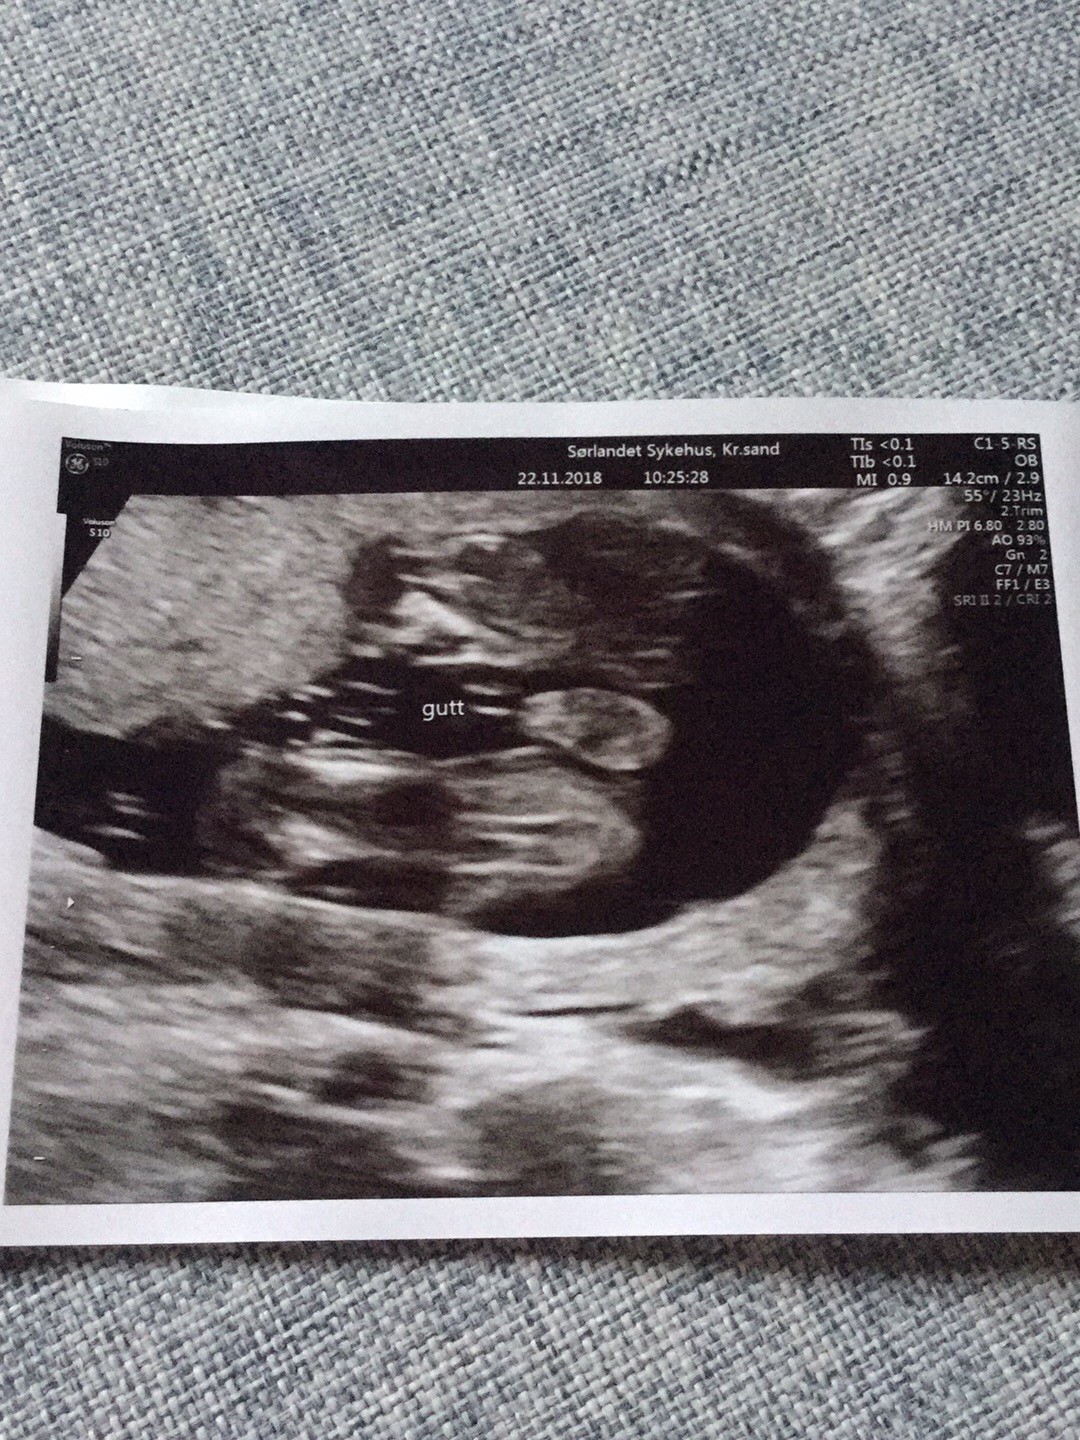

19+0 (wg usg i tego się teraz trzymamy!) wg OM 20+0

Waga : prawie 250 g i prawie 22 cm :biggrin2:

Tętno : 144(wczoraj), 150 (dzisiaj) :biggrin2:

Płeć : 100% chłopak :-) :)

Imię : Gabriel Mirosław :biggrin2:

Nosek - widoczny i śliczniutki (na prenatalnych podobno kośc nosowa była „nie do oceny”!)

Łożysko : na przedniej ścianie

Szyjka : 5 cm

Wszystkie narządy rozwijają się prawidłowo :-) :)

Termin porodu wg usg 20.04.2019 (jednak ze względu na cukrzycę typu2 nastąpi on 2 tygodnie wcześniej,ale konkretną datę poznam w późniejszym terminie) :-) :)